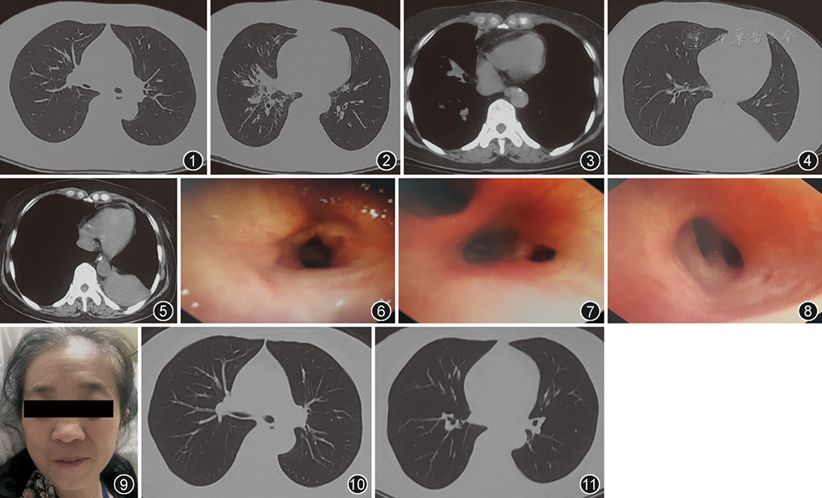

伴气管狭窄的复发性多软骨炎3例_刘静波

图片尺寸945x519